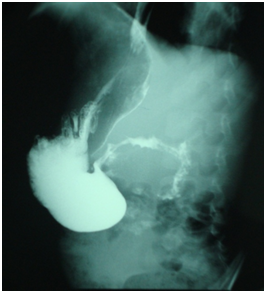

A two year old girl was presented in emergency for paroxystic abdominal pain without vomiting or other signs. The physical exam showed an epigastrium mass of 3cm which is round, tense, smooth and non tender beneath the umbilicus. Biologic exams were normal. Abdominal ultrasound with computer tomography revealed a cystic epigastric mass of 4.3cm with a wall that took contrast (Figure 3). Around this mass there was an ultrasound aspect of volvulus (Figure 4). A barium-meal examination demonstrated delayed gastric emptying through a narrowed pyloric antrum, which was distorted by a non communicating mass (Figure 5). At laparotomy, a cystic mass measuring approximately 4 × 3cm was identified anterior and lateral to the pyloric channel, sharing a common wall. The mass compressed the pyloric channel, resulting in partial gastric outlet obstruction. The duplication cyst did not communicate with the pyloric channel. Most of the cyst was excised, and the mucosa of the remnant cyst wall was cauterized. Histologic examination revealed gastric mucosa with a smooth muscle coat, which was consistent with a pyloric duplication cyst. No aberrant tissue was seen. The postoperative course was uneventful. The patient was asymptomatic 4years later.

Figure 5 A barium-meal examination: Narrowed pyloric antrum distorted from below by a non communicating mass.